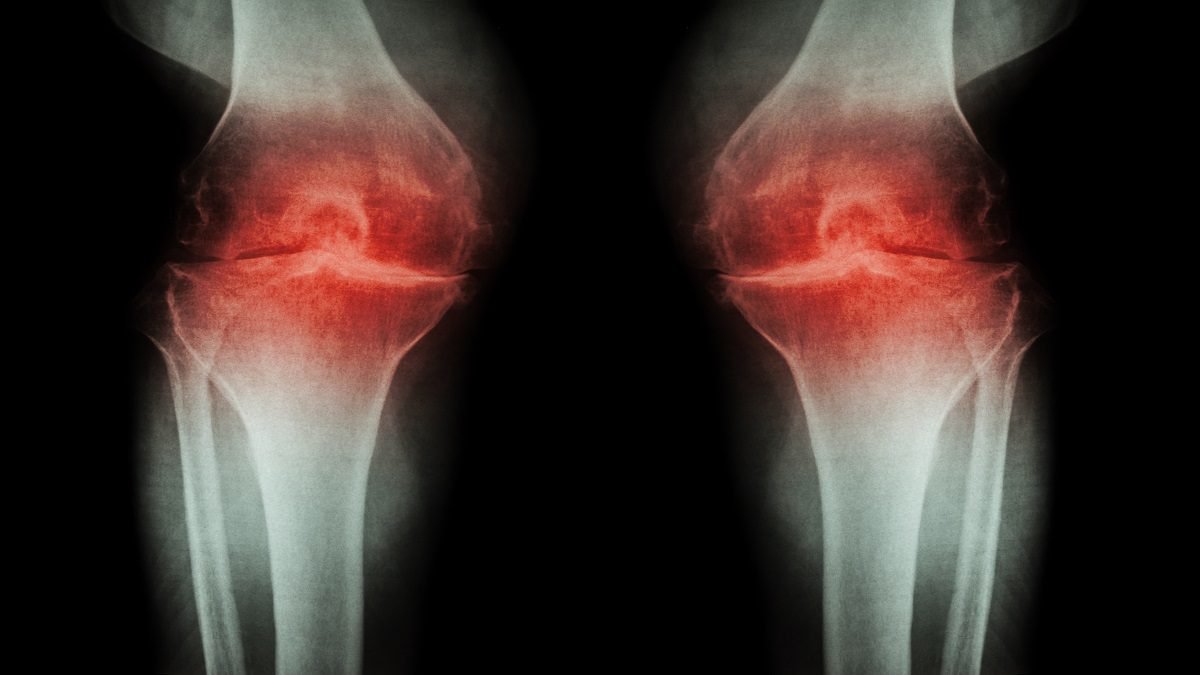

स्ट्रेस और एंग्जायटी की वजह से शरीर के जोड़ भी कमजोर होते हैं। अत्यधिक स्ट्रेस बॉडी इंफ्लामेशन बढ़ाता है। आर्थराइटिस के मरीजों के लिए तो दिक्कत ज्यादा हो सकती है। तनाव से शारीरिक काम भी कम हो जाता है, जिससे तकलीफ बढ़ सकती है।